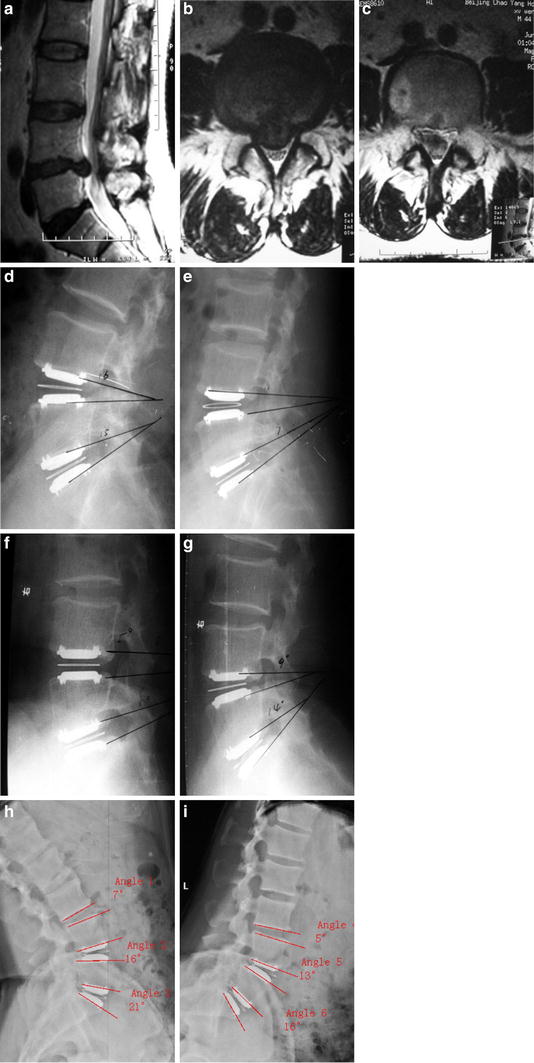

The charité artificial disc (depuy spine, inc.) was approved by the food and drug administration (fda) on october 26, 2004 for the treatment of severe low back pain due to a damaged or worn out. Lumbar total disc replacement using the charité artificial disc. James yue, rudolf bertagnoli, paul mcafee, howard an. The artificial disc, the first of its kind in the united states, was manufactured and marketed. Since the fda approved the artificial disc in october 2004, more than 5,000 people have received the implant, says depuy spine's bill christianson, vice president of regulatory affairs. The charité artificial disc, which is comprised of cobalt chromium endplates and ultra high molecular weight polyethylene (uhmwpe) sliding core, exhibits remarkable durability with. @article{mcafee2006revisabilityot, title={revisability of the charite artificial disc replacement. The unconstrained design of the charité artificial disc allows the mobile sliding core to translate 3 clinical neurosurgery volume 53, 2006the charité artificial disc: Another failed charite artificial replacement disc victim has contacted our office. Artificial disc replacement (adr), or total disc replacement (tdr), is a type of arthroplasty. Standards for testing artificial discs continue to evolve, and there are few detailed reports of conclusions: Artificial disc market size by type (cervical artificial disc, lumbar artificial disc), by material charite, the first disc implant used in total disc replacement, was created in germany in 1982. Artificial disc replacement surgery involves replacing a painful disc with an artificial disc. 26, the fda approved an implantable device (charité artificial disc, made by depuy spine, inc., a johnson & johnson company) for the replacement of damaged or worn out spinal discs in the. The charité artificial disc is designed to provide a new therapeutic option for treatment of degenerative disc disease as an alternative to spinal fusion to preserve function in the lumbar. Under these test conditions, the charité artificial disc produced minimal wear debris. The charité artificial disc (fig. Both types were manufactured in the former german democratic. 360° fusion via alif, plif, or tlif8 table adapted from: Backgroundcon text:lumbar arthroplasty with the charite artificial disc is approved in the u.s. The charite spinal disc is manufactured by depuy spine, a subsidiary company of johnson and johnson. Both types were manufactured in the former german democratic. The all and annulus were again sutured prior to closing the wound. It is the same story as, yet again, our newest client was promised the moon and has received a nightmare. Learn about the charité artificial disc replacement surgery procedure from dr. 17 patient satisfaction at 24 months, 74% of the patients with the. The charité artificial disc (depuy spine, inc.) was approved by the food and drug administration (fda) on october 26, 2004 for the treatment of severe low back pain due to a damaged or worn out. For decades there has been a desire to restore motion of a painful degenerated spinal segment. Conclusions lumbar tdr with the charite artificial disc did not preclude any further proce. Plication slightly more posterior in the disc space than the original implant. 5 the explanted charite´ artificial disc with no evidence of.